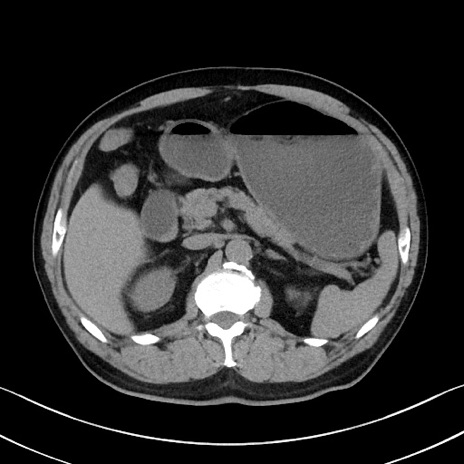

症例35(横断像)

【症例】70歳代 男性

【主訴】腹部膨満、嘔吐

【現病歴】昨日より腹部膨満感出現。本日増悪し、仙痛出現。嘔吐あり、受診。

【既往歴】糖尿病、胆摘後

【身体所見】BP 149/80mmHg、HR 74/min、BT 35.9℃、腹部:膨満、軟、圧痛なし。腸雑音減弱あり。上腹部正中切開瘢痕あり。

【データ】WBC 13500、CRP 1.72